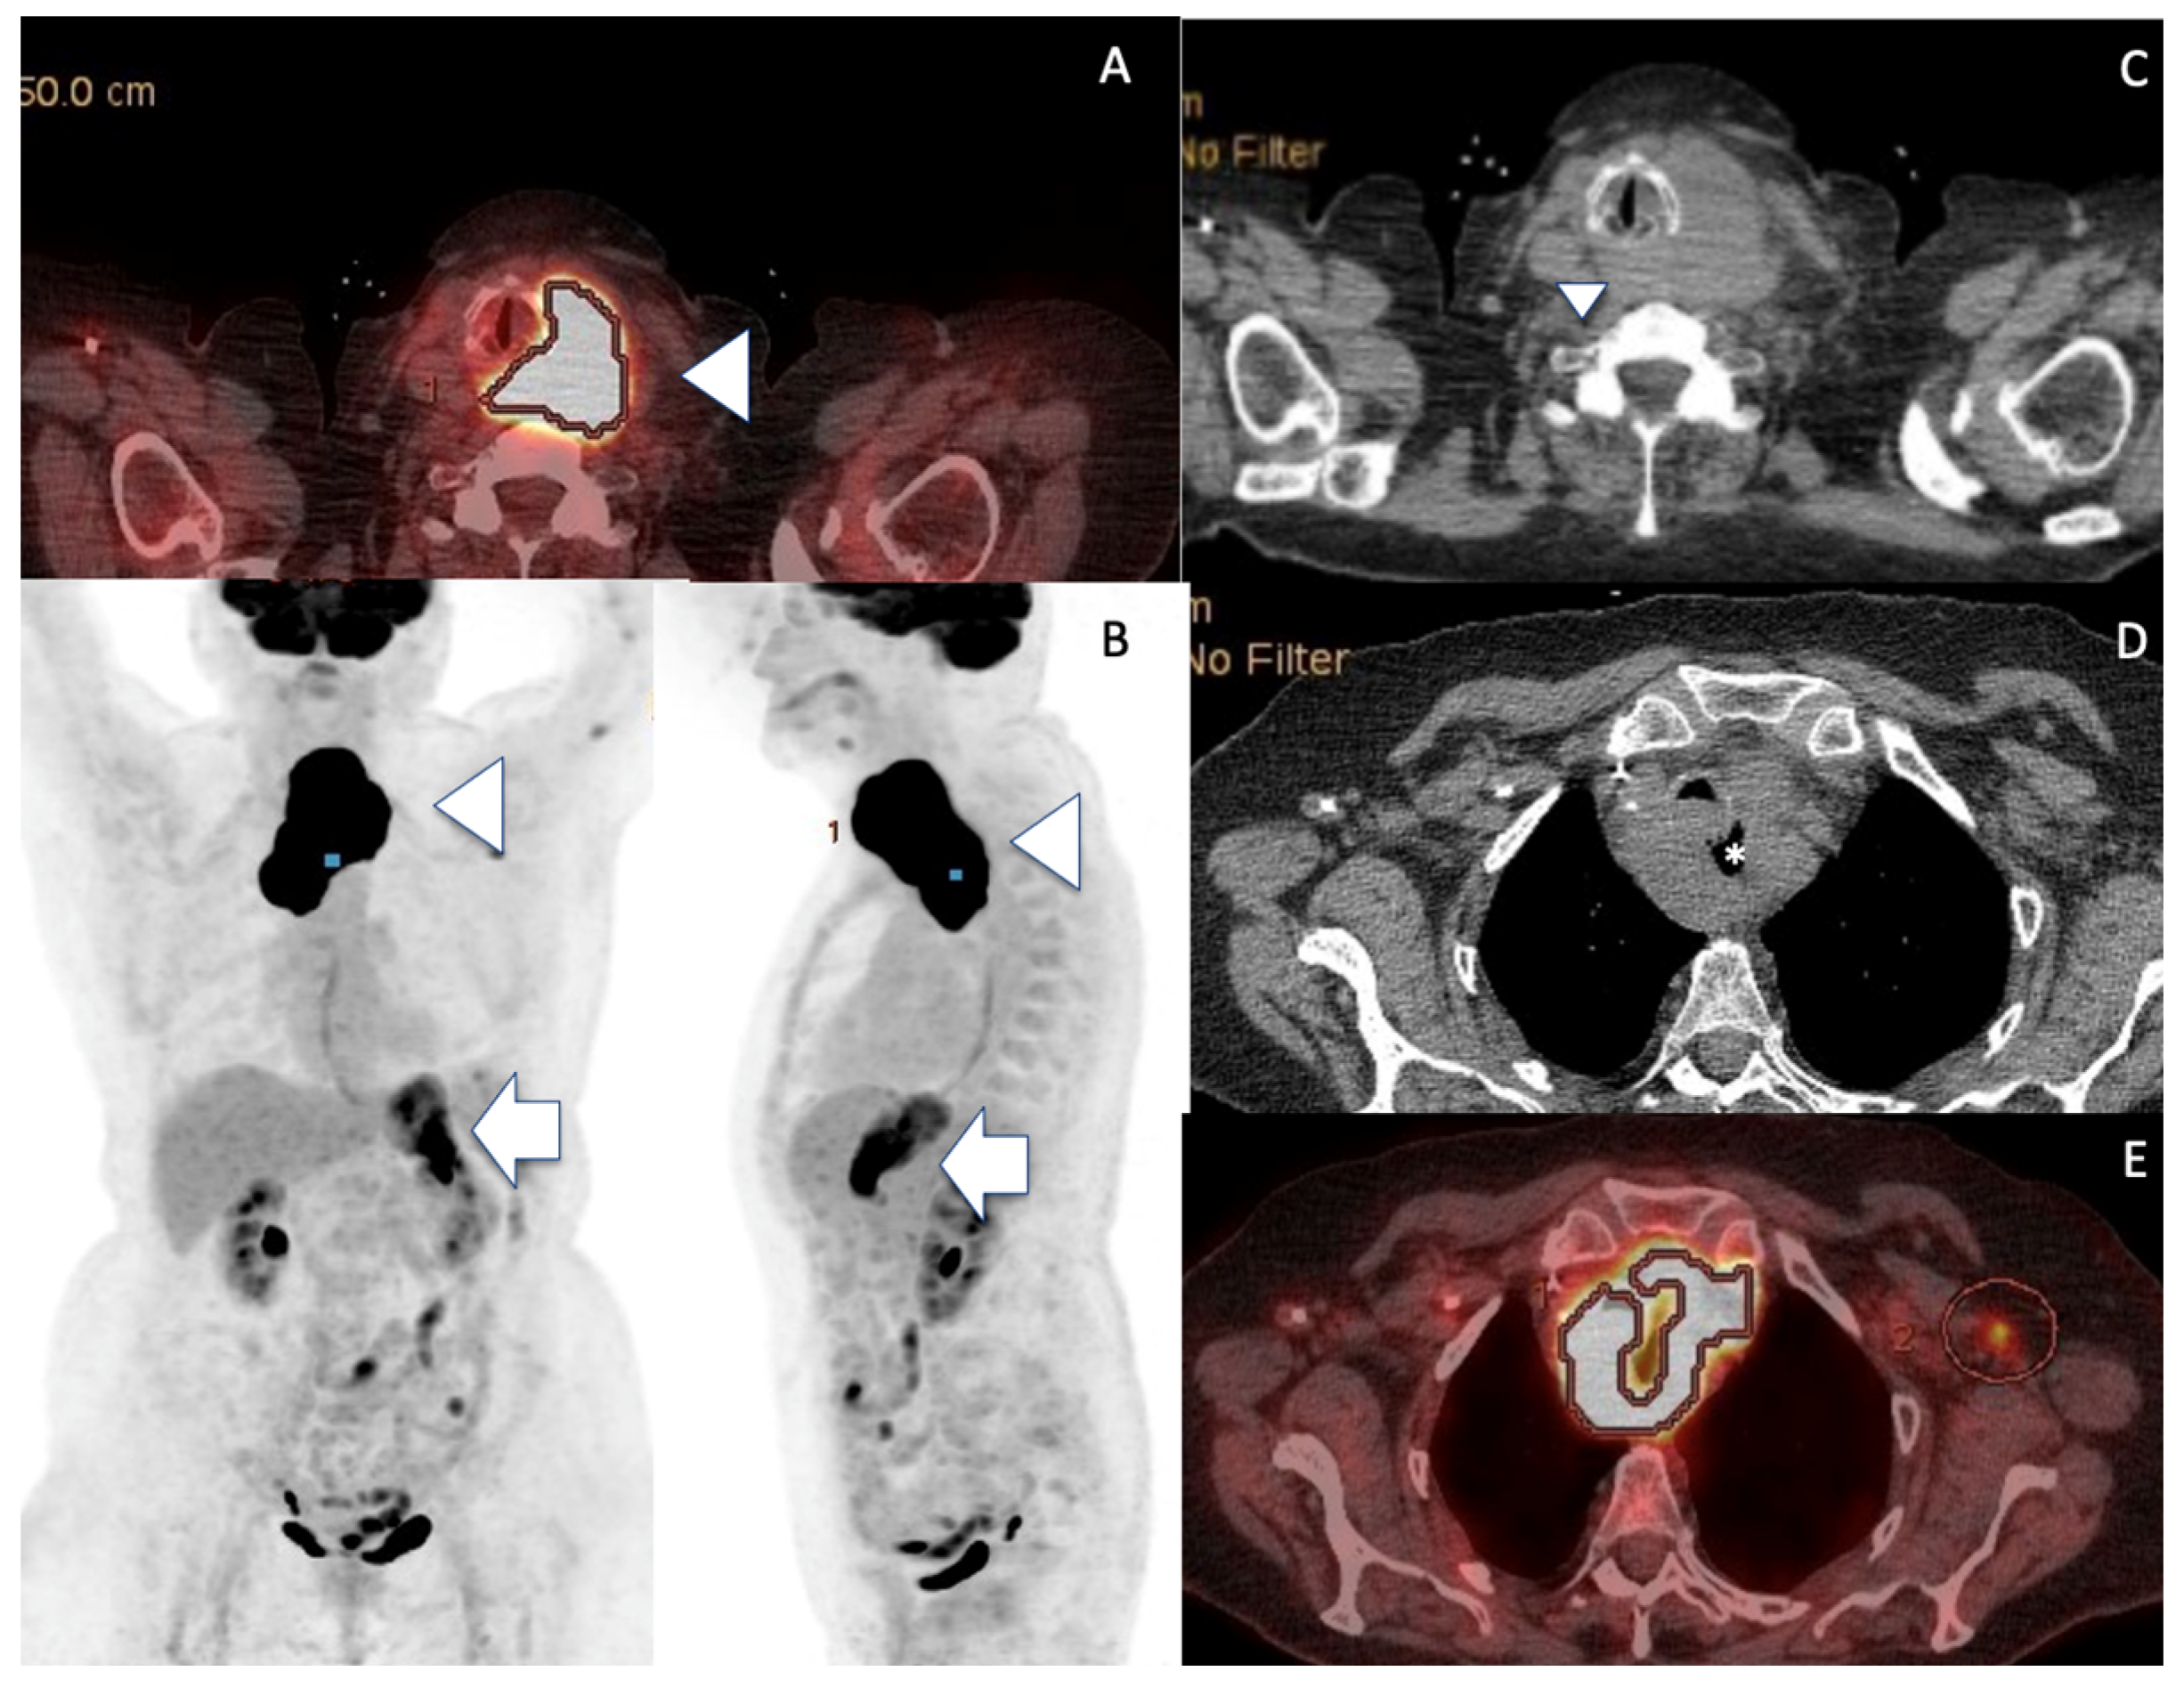

| Imaging Features US Doppler EuTIRADS score IJV invasion Computed Tomography | Reticular pattern More homogeneous than thyroid carcinoma No necrosis/calcification Sword sign Eu-TIRADS 5 Rare No cystic necrosis No gross calcification Homogeneous Nodes +/0 Mild vasculature Unclear boundaries + Vessel invasion not usual Tracheal compression + | No reticular pattern Heterogeneous Necrosis /calcification Sword sign Eu-TIRADS 5 Not rare Cystic necrosis Gross calcifications Heterogeneous Nodes ++/− Few vessels Unclear boundaries ++ Vessel invasion (33%) Tracheal compression ++ | No reticular pattern Inhomogeneous Depends on pre-existing thyroid No Sword sign Eu-TIRADS 5 > Eu-TIRADS 4 Exceptional No cystic necrosis No gross calcification Nodular Nodes +/− Increased Vasculature (renal) Unclear boundaries 0/+ Vessel invasion very rare (renal) Tracheal compression 0/+ |

| PET CT median SUVmax | +++ 22.7 | +++ 24.8 | ++/- variable |